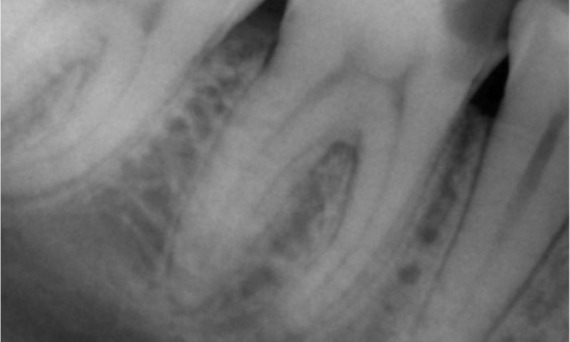

Antes: Tras el examen, hubo una lesión de caries relacionada con el primer molar inferior derecho. El examen radiográfico reveló la proximidad de la lesión a la bocina pulpar y, al combinarla con la queja principal, se concluyó un diagnóstico final de pulpitis irreversible crónica.

Después: La cavidad de acceso se realizó de la manera más conservadora posible. TruNatomy fue el sistema de elección debido a la edad del paciente joven. Necesitábamos preservar la dentina tanto como fuera posible para aumentar la capacidad del diente y así superar la carga oclusal y aumentar la longevidad de la restauración final.

Dr. Ahmed Hussein Abuelezz (PHD en endodoncia)

El Cairo, Egipto